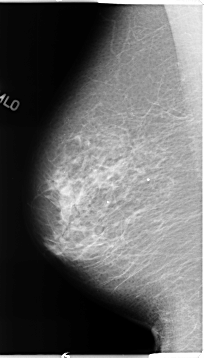

B_3123_1.LEFT_CC

LEFT_CC LINES 4680 PIXELS_PER_LINE 2288 BITS_PER_PIXEL 12 RESOLUTION 50 OVERLAY